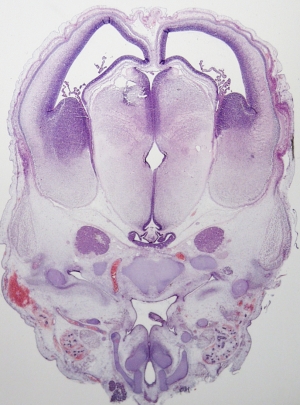

Stage 21

CfS 21

d37-39